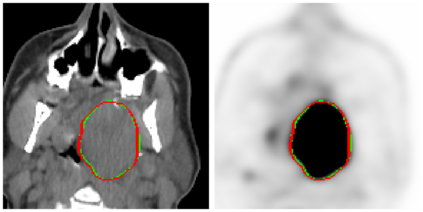

This paper presents an overview of the second edition of the HEad and neCK TumOR (HECKTOR) challenge, organized as a satellite event of the 24th International Conference on Medical Image Computing and Computer Assisted Intervention (MICCAI) 2021. The challenge is composed of three tasks related to the automatic analysis of PET/CT images for patients with Head and Neck cancer (H&N), focusing on the oropharynx region. Task 1 is the automatic segmentation of H&N primary Gross Tumor Volume (GTVt) in FDG-PET/CT images. Task 2 is the automatic prediction of Progression Free Survival (PFS) from the same FDG-PET/CT. Finally, Task 3 is the same as Task 2 with ground truth GTVt annotations provided to the participants. The data were collected from six centers for a total of 325 images, split into 224 training and 101 testing cases. The interest in the challenge was highlighted by the important participation with 103 registered teams and 448 result submissions. The best methods obtained a Dice Similarity Coefficient (DSC) of 0.7591 in the first task, and a Concordance index (C-index) of 0.7196 and 0.6978 in Tasks 2 and 3, respectively. In all tasks, simplicity of the approach was found to be key to ensure generalization performance. The comparison of the PFS prediction performance in Tasks 2 and 3 suggests that providing the GTVt contour was not crucial to achieve best results, which indicates that fully automatic methods can be used. This potentially obviates the need for GTVt contouring, opening avenues for reproducible and large scale radiomics studies including thousands potential subjects.